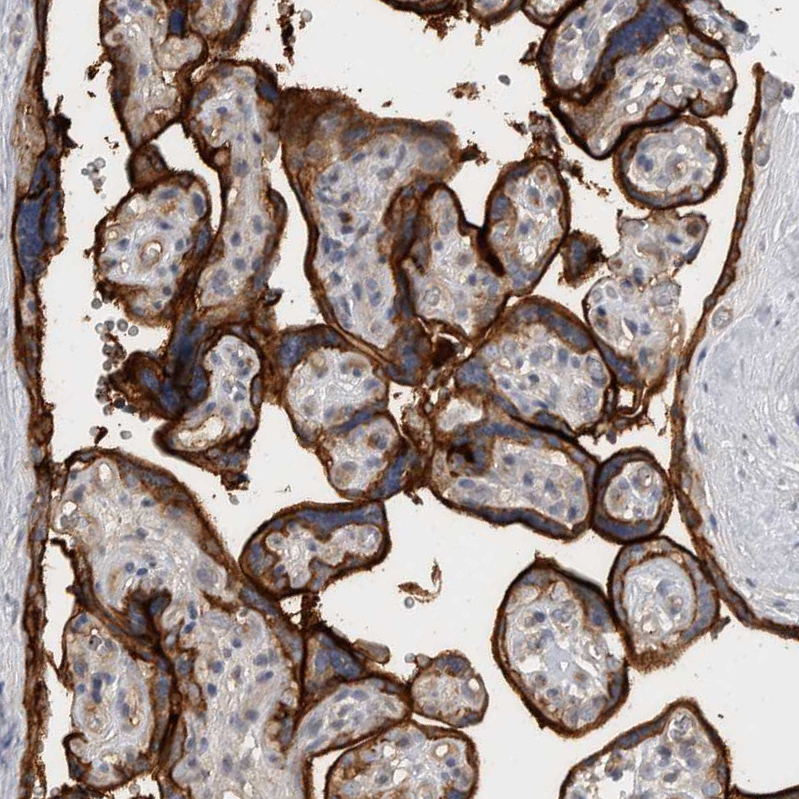

Immunohistochemical staining of human placenta shows strong membranous positivity in trophoblastic cells.